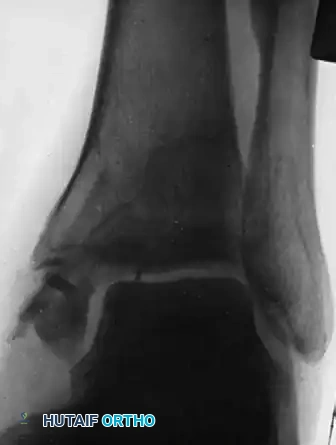

The following radiographic sequence illustrates the complex decision-making process in managing a recalcitrant medial malleolar nonunion.

Figure A: Demonstrates the ankle one month after an intraosseous autogenous bone grafting procedure was attempted for a chronic nonunion of the medial malleolus. Despite the intervention, the fracture line remains clearly visible, and the biological response is blunted.

FIGURE 59-17 A, One month after intraosseous graft for nonunion of fracture of medial malleolus.